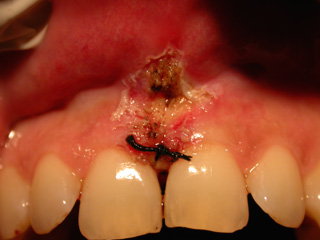

Esempio di frenulo labiale superiore che irrita papilla palatale

Un caso davvero particolare di una paziente (internet) che è venuta da noi per trattare una tumefazione sul palato che si era verificata in seguito alla ingestione di una bevanda particolarmente calda. Si nota un’inserzione bassa del frenulo labiale. La paziente si lamentava per la dolorosa infiammazione del tessuto edematoso (gonfiore) sollecitato dal contatto occlusale.